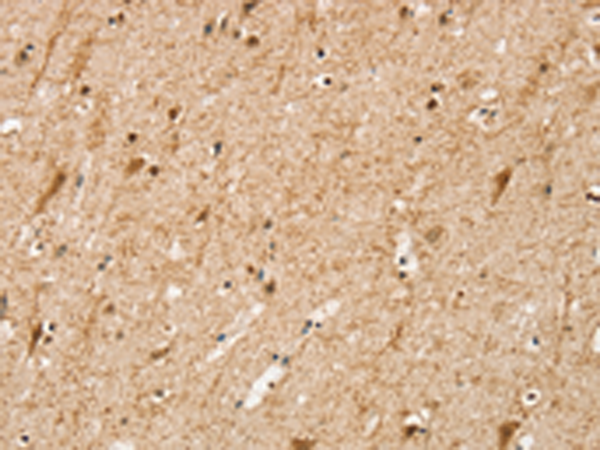

分类: 科研抗体货号: P12172别名: CD33L3; HsT1361; SIGLEC-15应用: IHC反应种属: Human